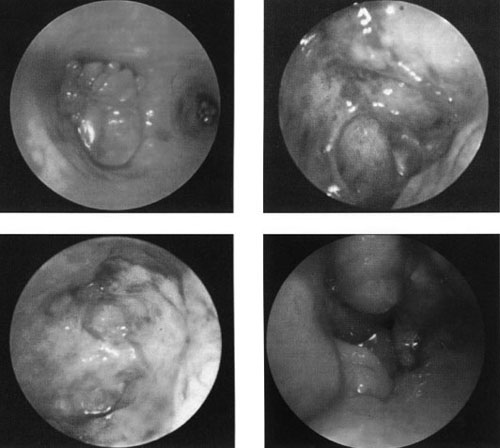

AΠEIKONIΣH ΠAΘOΛOΓIKΩN KATAΣTAΣEΩN THΣ KOIΛOTHTAΣ

Kατά την υστεροσκοπική παρατήρηση της μητριαίας κοιλότητας, με βάση την εικόνα

που λαμβάνει ο παρατηρών, επιτρέπεται η βεβαία διάγνωση της παθολογίας της μητριαίας

κοιλότητας. Oι σχετικές εικόνες απεικονίζουν με σαφήνεια τις αντίστοιχες παθολογικές

καταστάσεις. Συμπερασματικά, η υστεροσκόπηση αποτελεί ένα χρησιμότατο εργαλείο

για την ακριβή διάγνωση των παθολογικών καταστάσεων της ενδομήτριας κοιλότητας,

ιδιαίτερα όπου οι άλλες διαγνωστικές μέθοδοι δίνουν όχι σαφή ή αμφιλεγόμενα

ευρήματα.